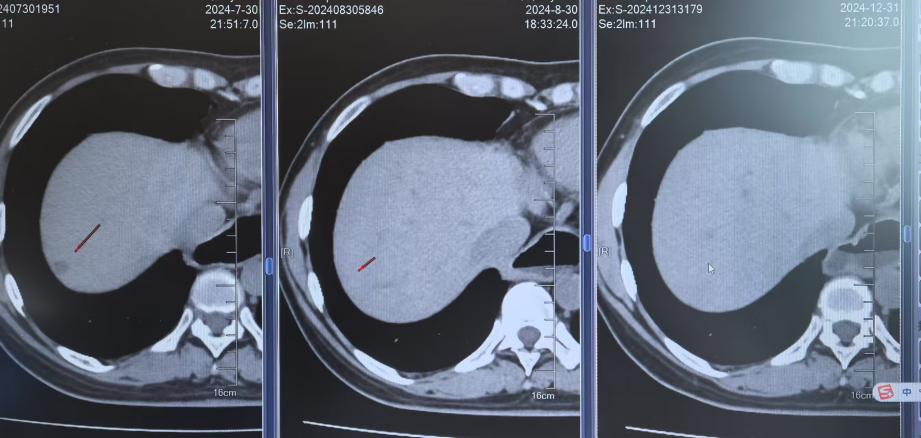

2024年7月30日胸部CT示:左上肺术区新增结节,两肺多发实性结节较前增多,肝S7新增结节;7月31日头颅MRI示左侧顶叶、小脑半球新增转移灶。结合影像及病史,确诊为ALK阳性晚期NSCLC复发伴多发转移(图1)。

影像学随访显示肺部、肝部的病灶完全消失,脑部的病灶缩小稳定;